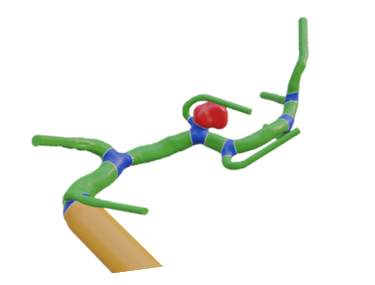

Vessel Tree Analysis

We want to develop an automatical vessel tree analysis tool for medical vascular structures. This is important for tumor surgery planning (which vessel should be spared? which vessel is at risk by the tumor location? …) but also for stroke analysis (which vessel supporting the brain might be hampered?).

Virtual Reality for Surgery Planning

We are looking for a student interested in developing virtual reality (VR) applications using Unity for support of liver surgery planning. The VR project should include gamification aspects (like high scores etc.) to engage the medical users and increase their motivation.